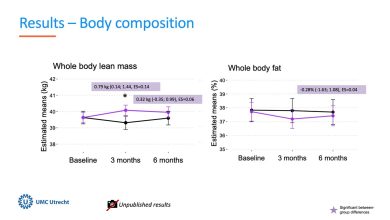

Estudo mostra que o exercício supervisionado melhora a força e o desempenho físico em pacientes com câncer de mama avançado

A massa magra de todo o corpo, que é um indicador da massa muscular, aumentou no grupo de exercício, enquanto…